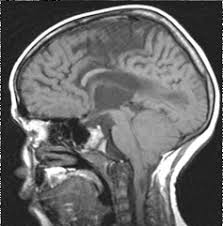

Chiari Ii